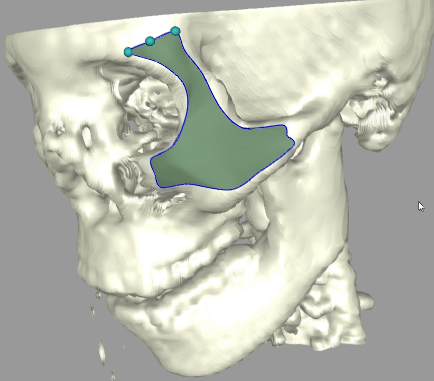

Sketch-Line Interactions for 3D Image Visualization and Analysis, T. McInerney and Y.S. Shih, 9th International Symposium on Visual Computing (ISVC 2012), Rethymnon, Crete, Greece, Jul. 2012, pages 686-697. |

SketchSurfaces: Sketch-Line Initialized Deformable Surfaces for Efficient and Controllable

Interactive 3D Medical Image Segmentation,

M. Aliroteh and T. McInerney, International Symposium on Visual Computing (ISVC), Lake Tahoe, NV, Nov. 2007.

Sketch Initialized Snakes for Rapid, Accurate, and Repeatable Interactive Medical Image Segmentation,

T. McInerney and M.R. Akhavan Sharif,2006 IEEE International Symposium on Biomedical Imaging, Arlington, Virginia, April 2006, pages 398-401.